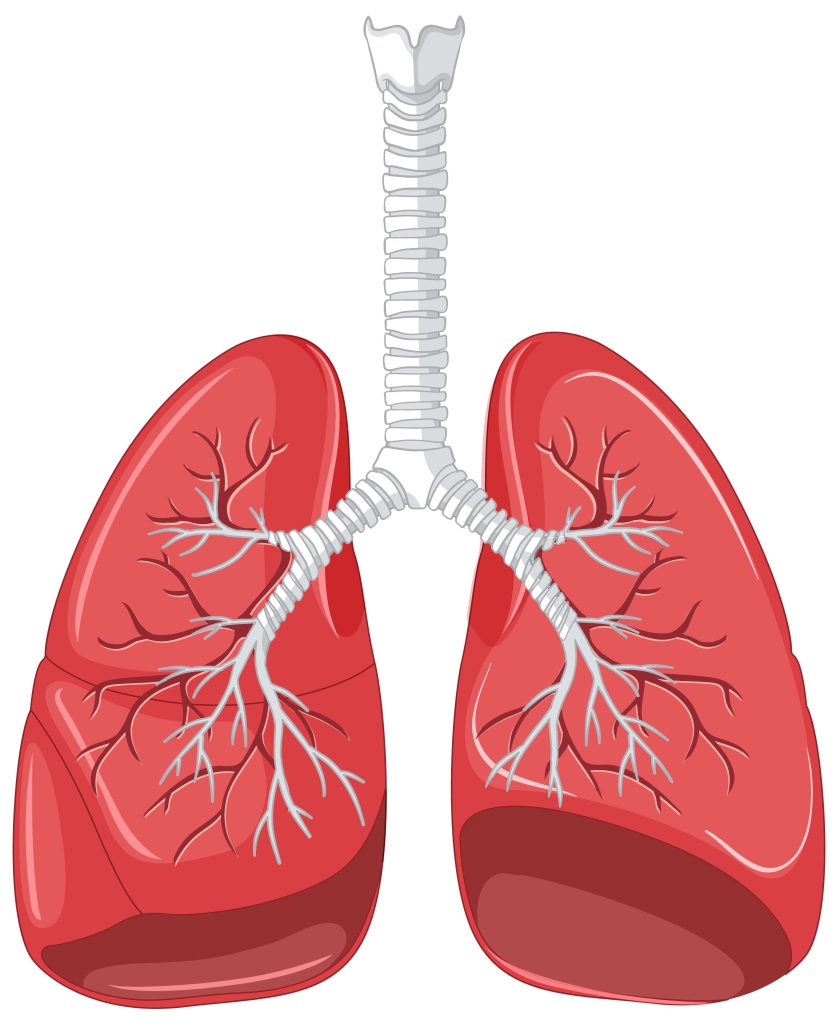

Akupunktur adalah bagian penting dari pengobatan tradisional Tiongkok yang telah digunakan selama ribuan tahun untuk menjaga keseimbangan energi tubuh (Qi) dan mengobati berbagai macam gangguan kesehatan. Salah satu jalur utama dalam sistem meridian tubuh adalah meridian paru-paru (Lung Meridian / LU), yang memiliki peran penting dalam sistem pernapasan dan imunitas tubuh.

Meridian paru-paru adalah salah satu dari dua belas meridian utama dalam tubuh manusia. Jalur energi ini dimulai dari dada bagian atas, bergerak ke lengan bagian dalam, dan berakhir di ujung ibu jari. Meridian ini berhubungan langsung dengan fungsi paru-paru, kulit, hidung, serta sistem kekebalan tubuh.

Ketidakseimbangan pada meridian paru-paru dapat menyebabkan gejala seperti batuk, sesak napas, pilek, asma, kelelahan, hingga masalah pada kulit.

Meridian paru-paru memegang peran penting dalam menjaga kesehatan sistem pernapasan dan pertahanan tubuh. Melalui teknik akupunktur, titik-titik pada meridian ini dapat distimulasi untuk mengatasi berbagai keluhan fisik maupun emosional. Penting untuk melakukan terapi ini dengan praktisi akupunktur yang berlisensi dan berpengalaman agar hasilnya optimal dan aman.